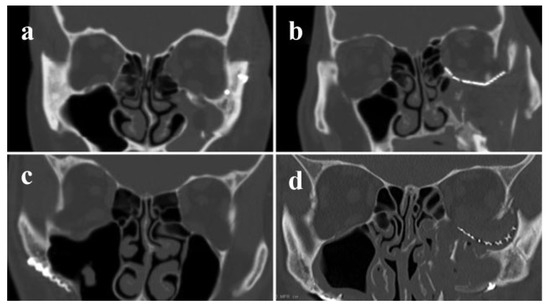

Figure 1.

Coronal views of postoperative computed tomography facial scans are shown for patients without (a,b) and with (c,d) postoperative complications.